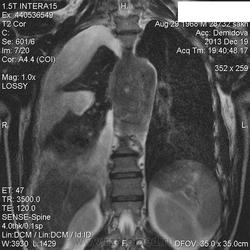

Да, интересно, и интрадуральный рост есть и контуры нечеткие, нужен дифряд на мой взгляд. А почему у вас такие картинки нечеткие? Особенно Т2 корон, и аксиалы? Наверное нужно отрегулировать параметры программ сканирования ( не спрашивайте меня что именно :-) ) в сентябре было не все гладко, больше чем уверена, а снимков у вас нет?

Инженер в отпуске , наверное, поэтому такие вот нечеткие.Я в аппликаторском деле не Копенгаген.

И я Вас приветствую ))), а толщину среза какую ставите на коронарные срезы? У нас такой же аппарат и качество совсем отличается, аппликаторы настраивали программы. Так что, советую задать им вопрос.

5 мм.

Не пробовали поменьше толщину среза делать? Я иногда делаю три и даже два мм, и количество срезов поменьше, когда что то нужно показать типа опухоли с прорастанием , получается красиво. А чтоб артефакты от дыхательных движений убрать это к инженеру или аппликаторам вопрос. Я тоже не Копенгаген :-).

Светлана, у нас вообще коронал в обязательные программы не входит, это я уже сказала сделать, чтобы посмотреть получше и заключение мало-мальски оформить.По идее , нужно было органы средостения делать-там толщина среза поменьше, но пациенту было назначено именно ГОП, заплачено тоже за него.